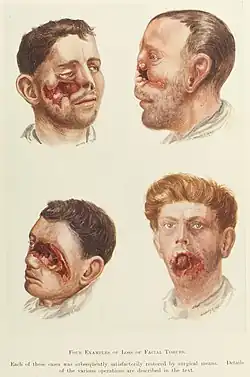

Etwa 500 Jahre später verfasste Ambroise Paré (1510–1590)[109] zahlreiche und sich weit verbreitende Beiträge in französischer, und somit auch nichtakademisch gebildeten Wundärzten und Barbieren verständlicher Sprache zur Zahnbehandlung. Für wichtig hielt Paré die Grundsätze, dass Überflüssiges entfernt, ein fauler Zahn extrahiert werden muss und Fehlendes ersetzt (reimplantiert) wird.[110] Er entwickelte stabilisierende Ligaturen für Kieferfrakturen, experimentierte mit der Wiederbefestigung herausgeschlagener Zähne und konstruierte einfachen, festsitzenden Zahnersatz. Er prägte den Begriff „Obturateur“. Obturatoren dienten dem Verschluss von Gaumendefekten, die häufig eine Folge der tertiären Syphilis waren. Sie bestanden aus Leder, Silber, Elfenbein oder einem Schwamm, der an einem Metallhalter befestigt war.